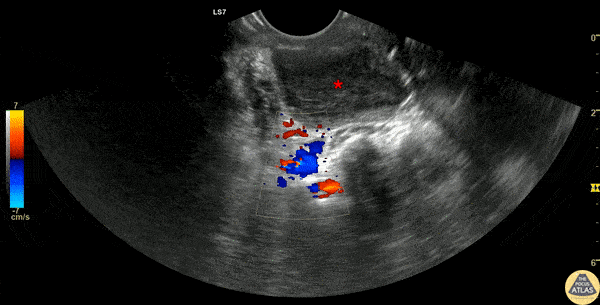

30s F presented with a week of sore throat which had not improved despite corticosteroids and antibiotics. She was referred to the ED by her primary care provider who noted asymmetric swelling in her throat and had concern for peritonsillar abscess (PTA). Evaluation in the ED confirmed this finding, and POCUS was performed, demonstrating a large PTA. The first half of this clip shows a transverse view of the peritonsillar space, where a circumscribed heterogeneous hypoechoic region is seen superficially, which is the PTA (*). Color doppler identifies the carotid artery posterior to the PTA, a critical structure to identify to prevent inadvertent arterial puncture or laceration. The second half of the clip shows the PTA after needle aspiration of 15cc purulence, demonstrating a collapsed abscess cavity with scattered air and significantly reduced abscess size. The patient had immediate relief of her symptoms after needle aspiration, and was discharged with antibiotics and outpatient ENT follow up. Dr. Michael Heffler, PGY-4 Denver Health Residency in Emergency Medicine